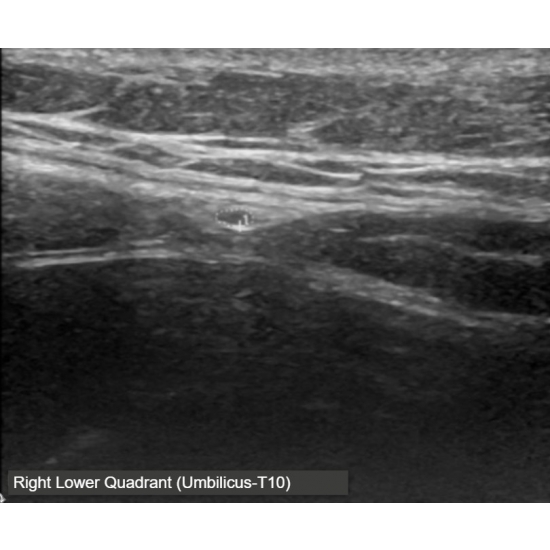

Pelvis ultrasound, CT abdomen/pelvis, MRI abdomen/pelvis and MRI total spine were performed and showed no evidence of acute pathology. The patient underwent a diagnostic ultrasound in clinic which revealed signs of anterior cutaneous nerve entrapment, including hourglass narrowing, loss of echotexture and enlargement of the nerve at the level of entrapment. Ultrasound images included below demonstrate the difference in cross sectional area between the left and right anterior abdominal cutaneous nerve, respectively; note the slight variation in the course of the nerve as it traverses the fibrous band within the rectus abdominis.

Case Photo #1 , Case Photo #2